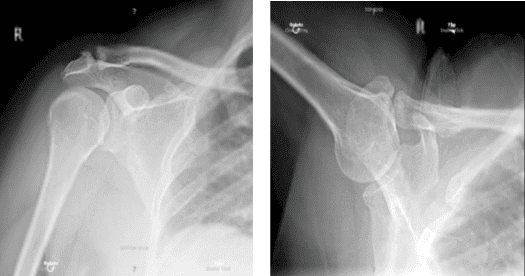

La paciente es una mujer de 54 años que entró en la consulta tras caerse y no poder mover el hombro. Estaba muy incómoda. El examen reveló una rotura del manguito rotador. Una resonancia magnética reveló una importante rotura del manguito rotador en el hombro izquierdo, así como una subluxación del bíceps.

Hombros bilaterales de rayos X